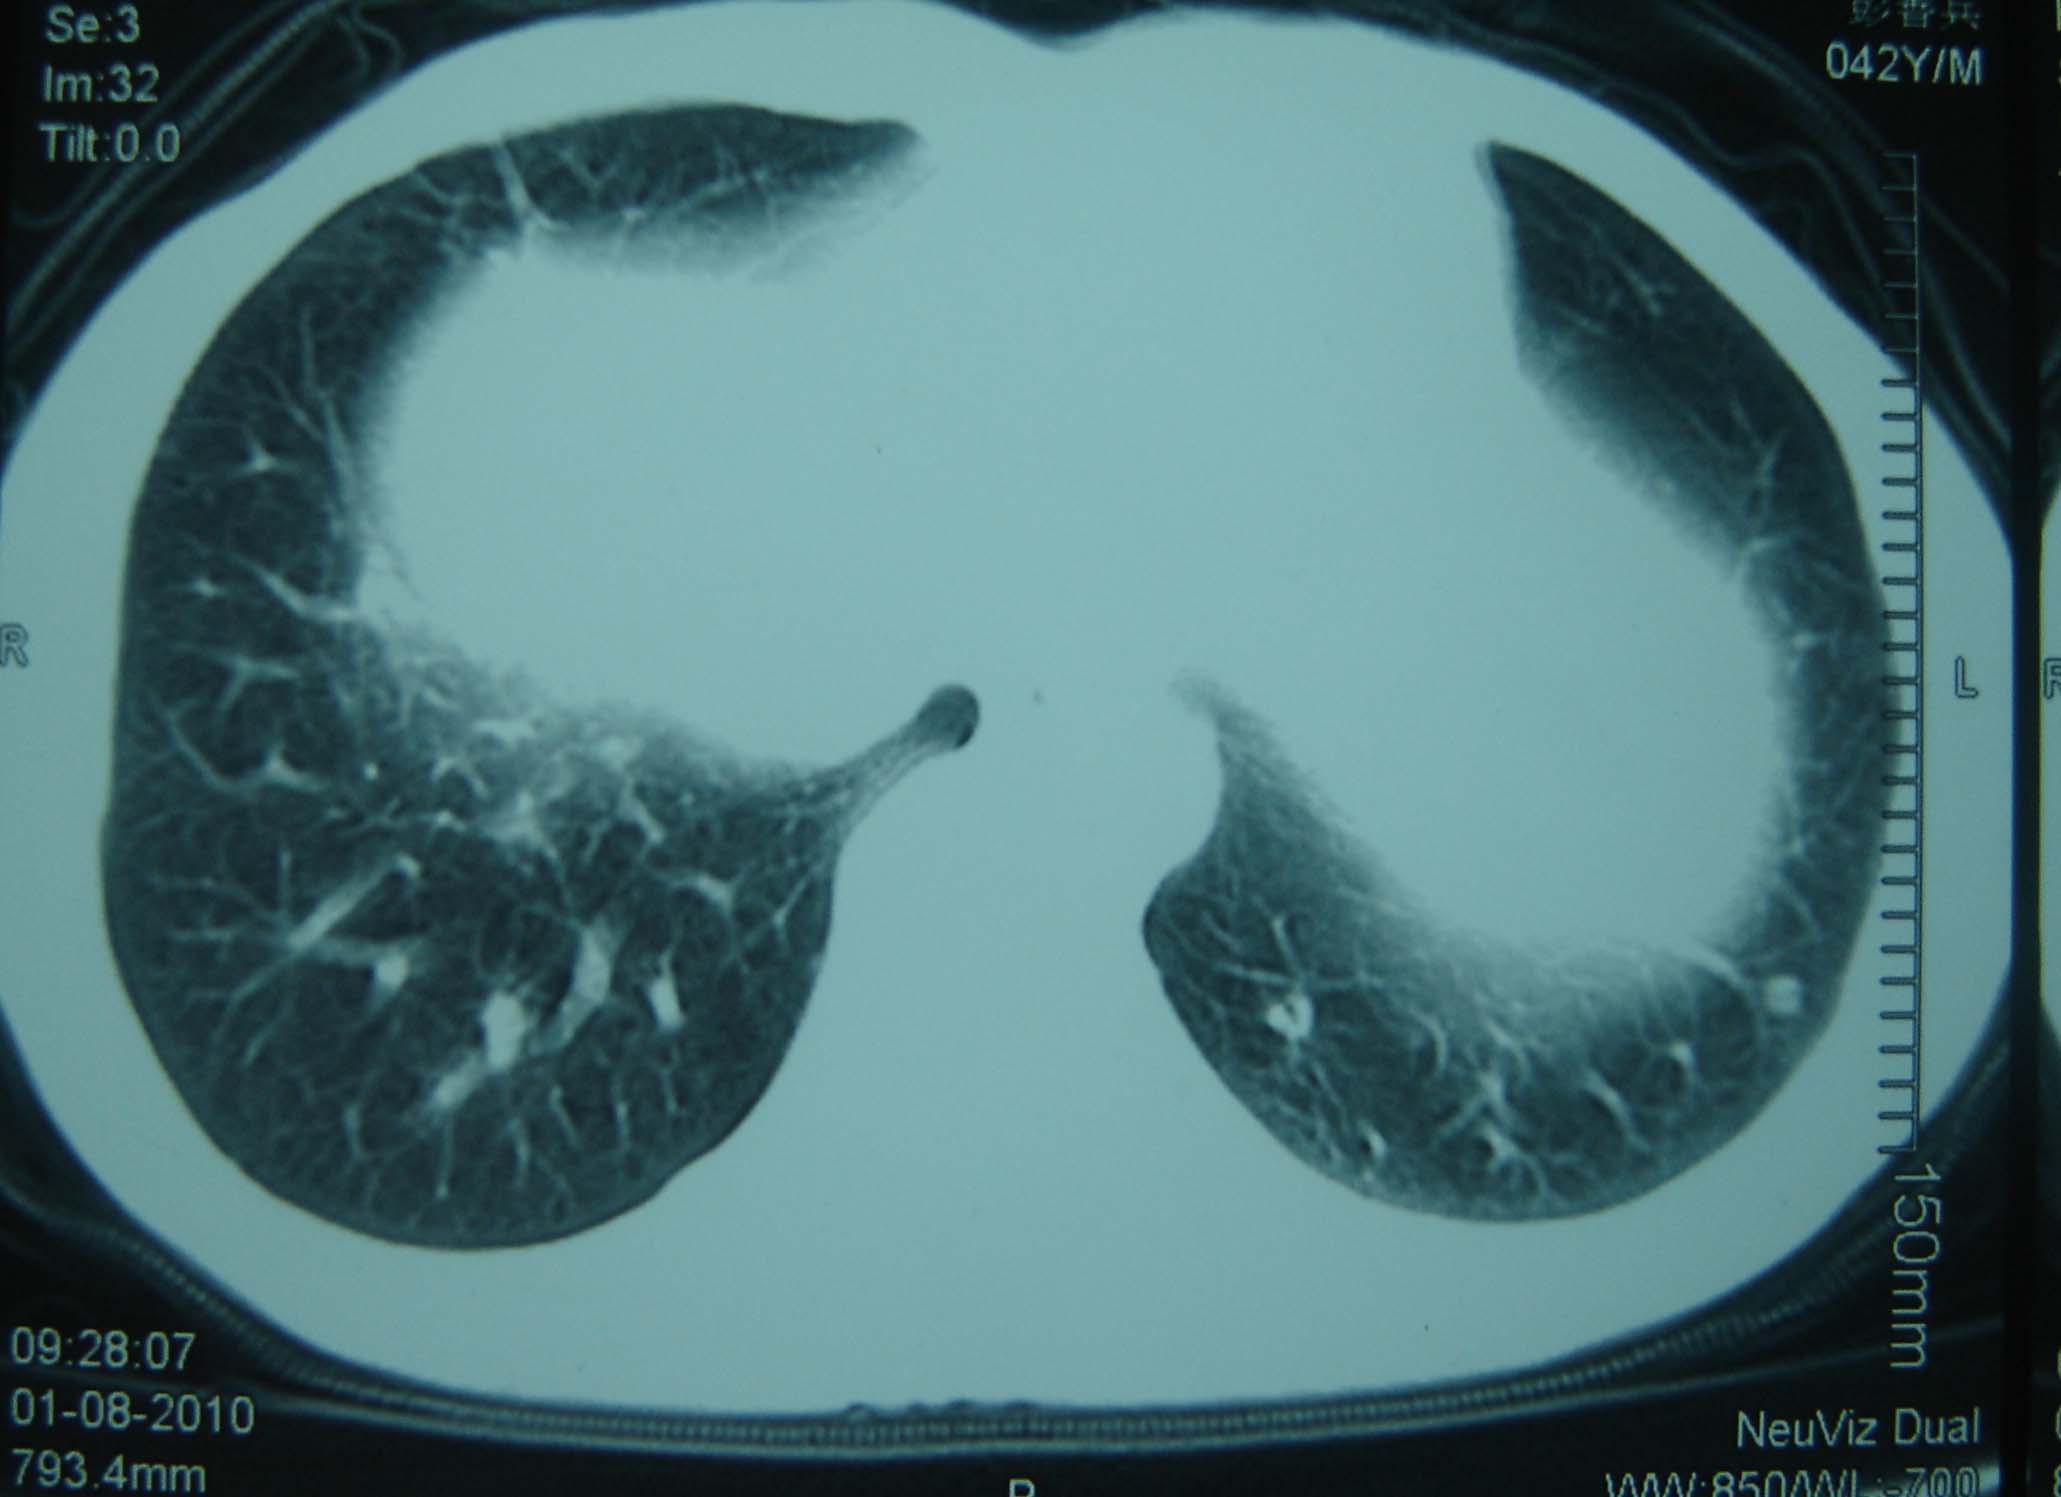

标题: CT25321:两肺多发结节 请会诊 [打印本页]

标题: CT25321:两肺多发结节 请会诊

男 、43岁,咳嗽胸痛,装修工,平时接触粉尘较多,有吸烟史10多年,纤维支气管镜检查未发现异常,胃镜、腹部b超检查亦未发现异常,颈部淋巴结活检未发现肿瘤细胞。

不能排除转移,如果不能找到原发灶,只有短期随访。

结节病?转移瘤?

1)考虑双肺及胸膜多发性转移瘤。2)肺气肿。